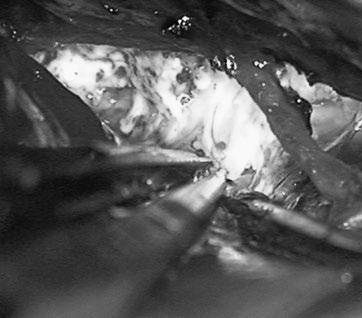

他紧急行半侧颅骨切除术,随后血管造影显示右侧动脉瘤,AVM由双侧PcaA供血,引流向前MedFrV和SplenV【左侧ICA像,(a)前后位(b)侧位】(c)首先通过双侧开颅并排夹闭动脉瘤(鼻朝右,中线呈水平,重力牵开右侧额叶),然后切开动脉瘤使之缩小。